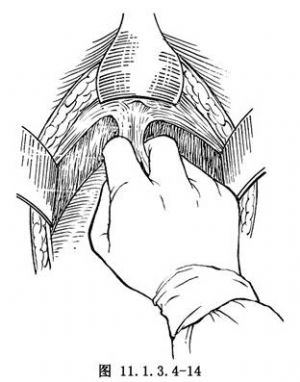

(3)從恥骨聯合後,鈍性剝離膀胱前間隙,對膀胱恥骨韌帶結締組織束可剪斷,使膀胱完全從恥骨後面分離。以示、中指探觸膀胱頸及尿道(圖11.1.3.4-14)。助手自陰道經導尿管向氣囊充氣,後牽引導尿管,遇阻力處即爲膀胱頸。繼續向下剝離,直到近尿道外口。